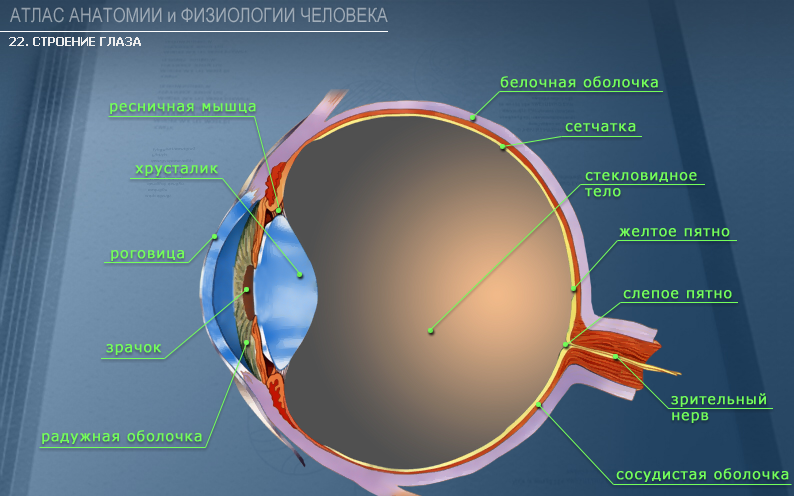

Изображения и анатомия сетчатки глаза

Раздел: Визуальный дайджест